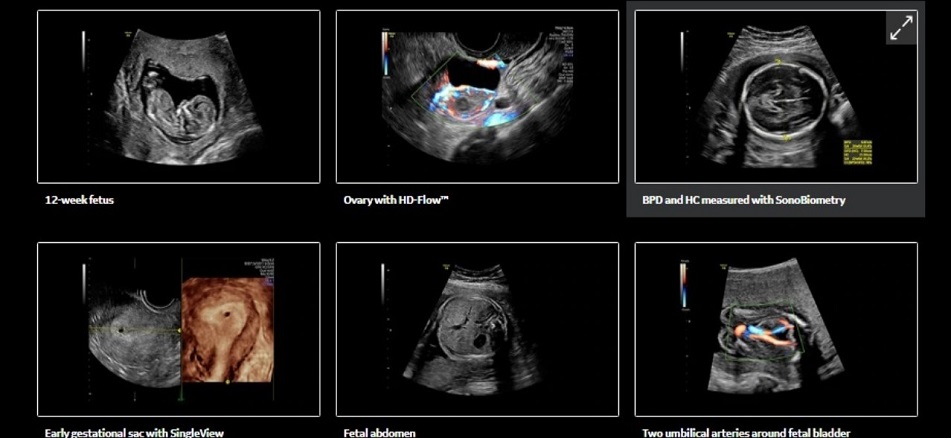

Máy siêu âm Doppler màu, máy siêu âm 4D Voluson P8… cho các thông số chính xác về sức khỏe mẹ và bé